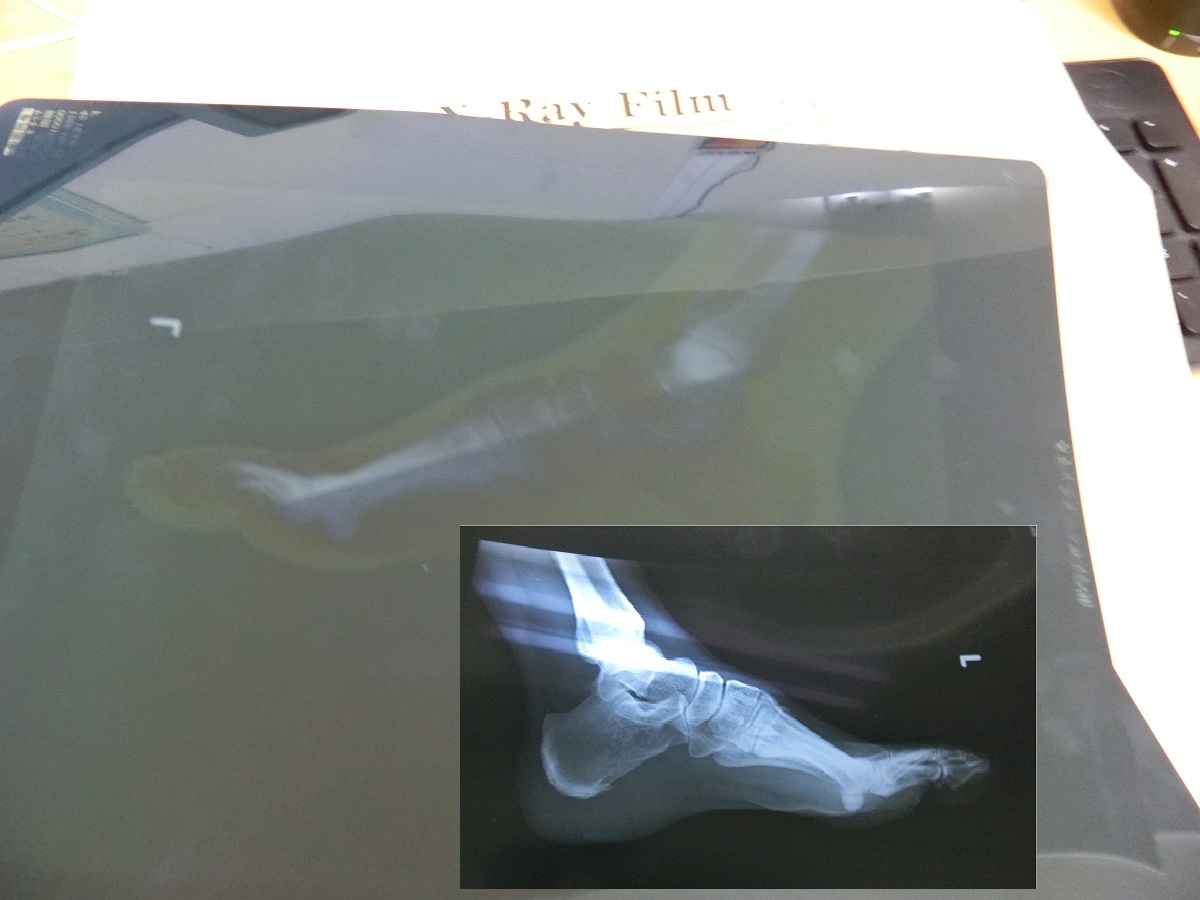

足の専門外来で診てもらったら、『踵に棘が出来ています(踵骨棘)』と診断をもらった

写真には確かに左の踵の骨に棘が小さく映っていた

足は、「ハイアーチ」であったが左足はどうも回内が強く踵の動きに問題があるようであった